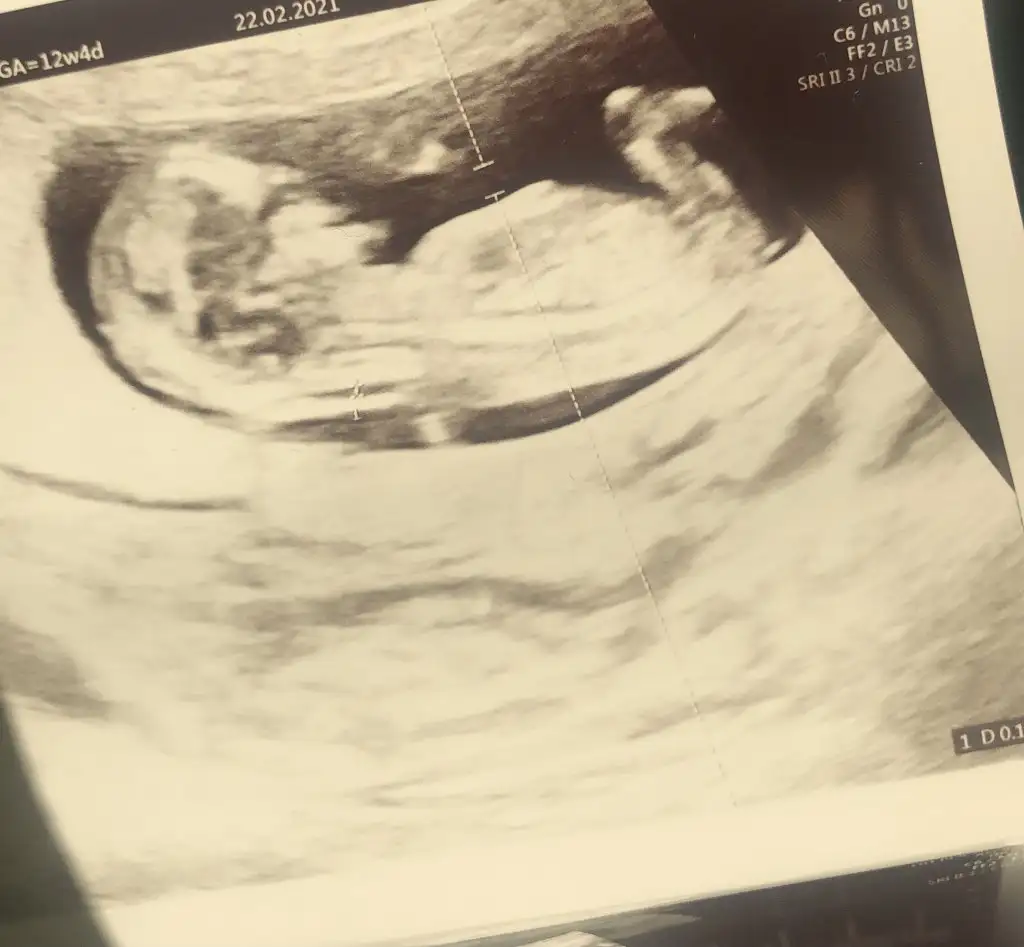

Benim bi tane hemşire komsum var, 8.hafta bitince artık bir şey olmaz demişti. Ne diyo lan bu dedim içimden ama hala 12.haftayı atlatalım, tarama testini atlatalım, cinsiyeti öğrenelim diye diye bu hafta ettik. Kadın boşuna hemşire olmamış diyorum şimdi dediği gibi oldu valla🤣

Ilk 8 hafta aslında kalp durmalarinın falan en sık görüldüğü haftalar. Ileriki haftalarda görülen gebelik kayıpları daha çok bebekten değil anneden kaynaklı rahimde kısalma oluyor açılma oluyor hep de önlenebilir şeyler. Aslında 8.hafta ilk basamak yani, 12.hafta ikinci basamak. Artık bir şey olmayacak Allahın izniyle 🥰🥰🧿🧿🧿

Burdan bi de herkese sesleniyorum, kizlar 12. hafta bitince her kontrolde rahim uuzunlugunuzu ölçtürün. 25 mm altına inmediği sürece dinlenip progesteron desteğiyle uzatabilirsiniz ama fark etmeden 25 mm altına inerse sıkıntılı.

Ya evet aslında Bi yandan doğru çoğu kayıp hep 8. Haftalara kadar oluyormuş. Şükür bu zamana gelene kadsr hep tetikreydim. Doktor erken kanama olursa hemen gel dedi uyuşmazlık iğnesini yapacakmış bizde rh uyumsuzluğu var belki o yüzden Bi kanama yaşayabilirim diyorum ama bakalım. İnşallah birşey olmaz artık bacım sağolasın 🥰🙏🏻 şu ikili testi de sağlıcakla atlatsam inşallah risk falan yoktur. Bu arada o rahim uzunluğunu nasıl ölçüyor doktor karından usg ile mi